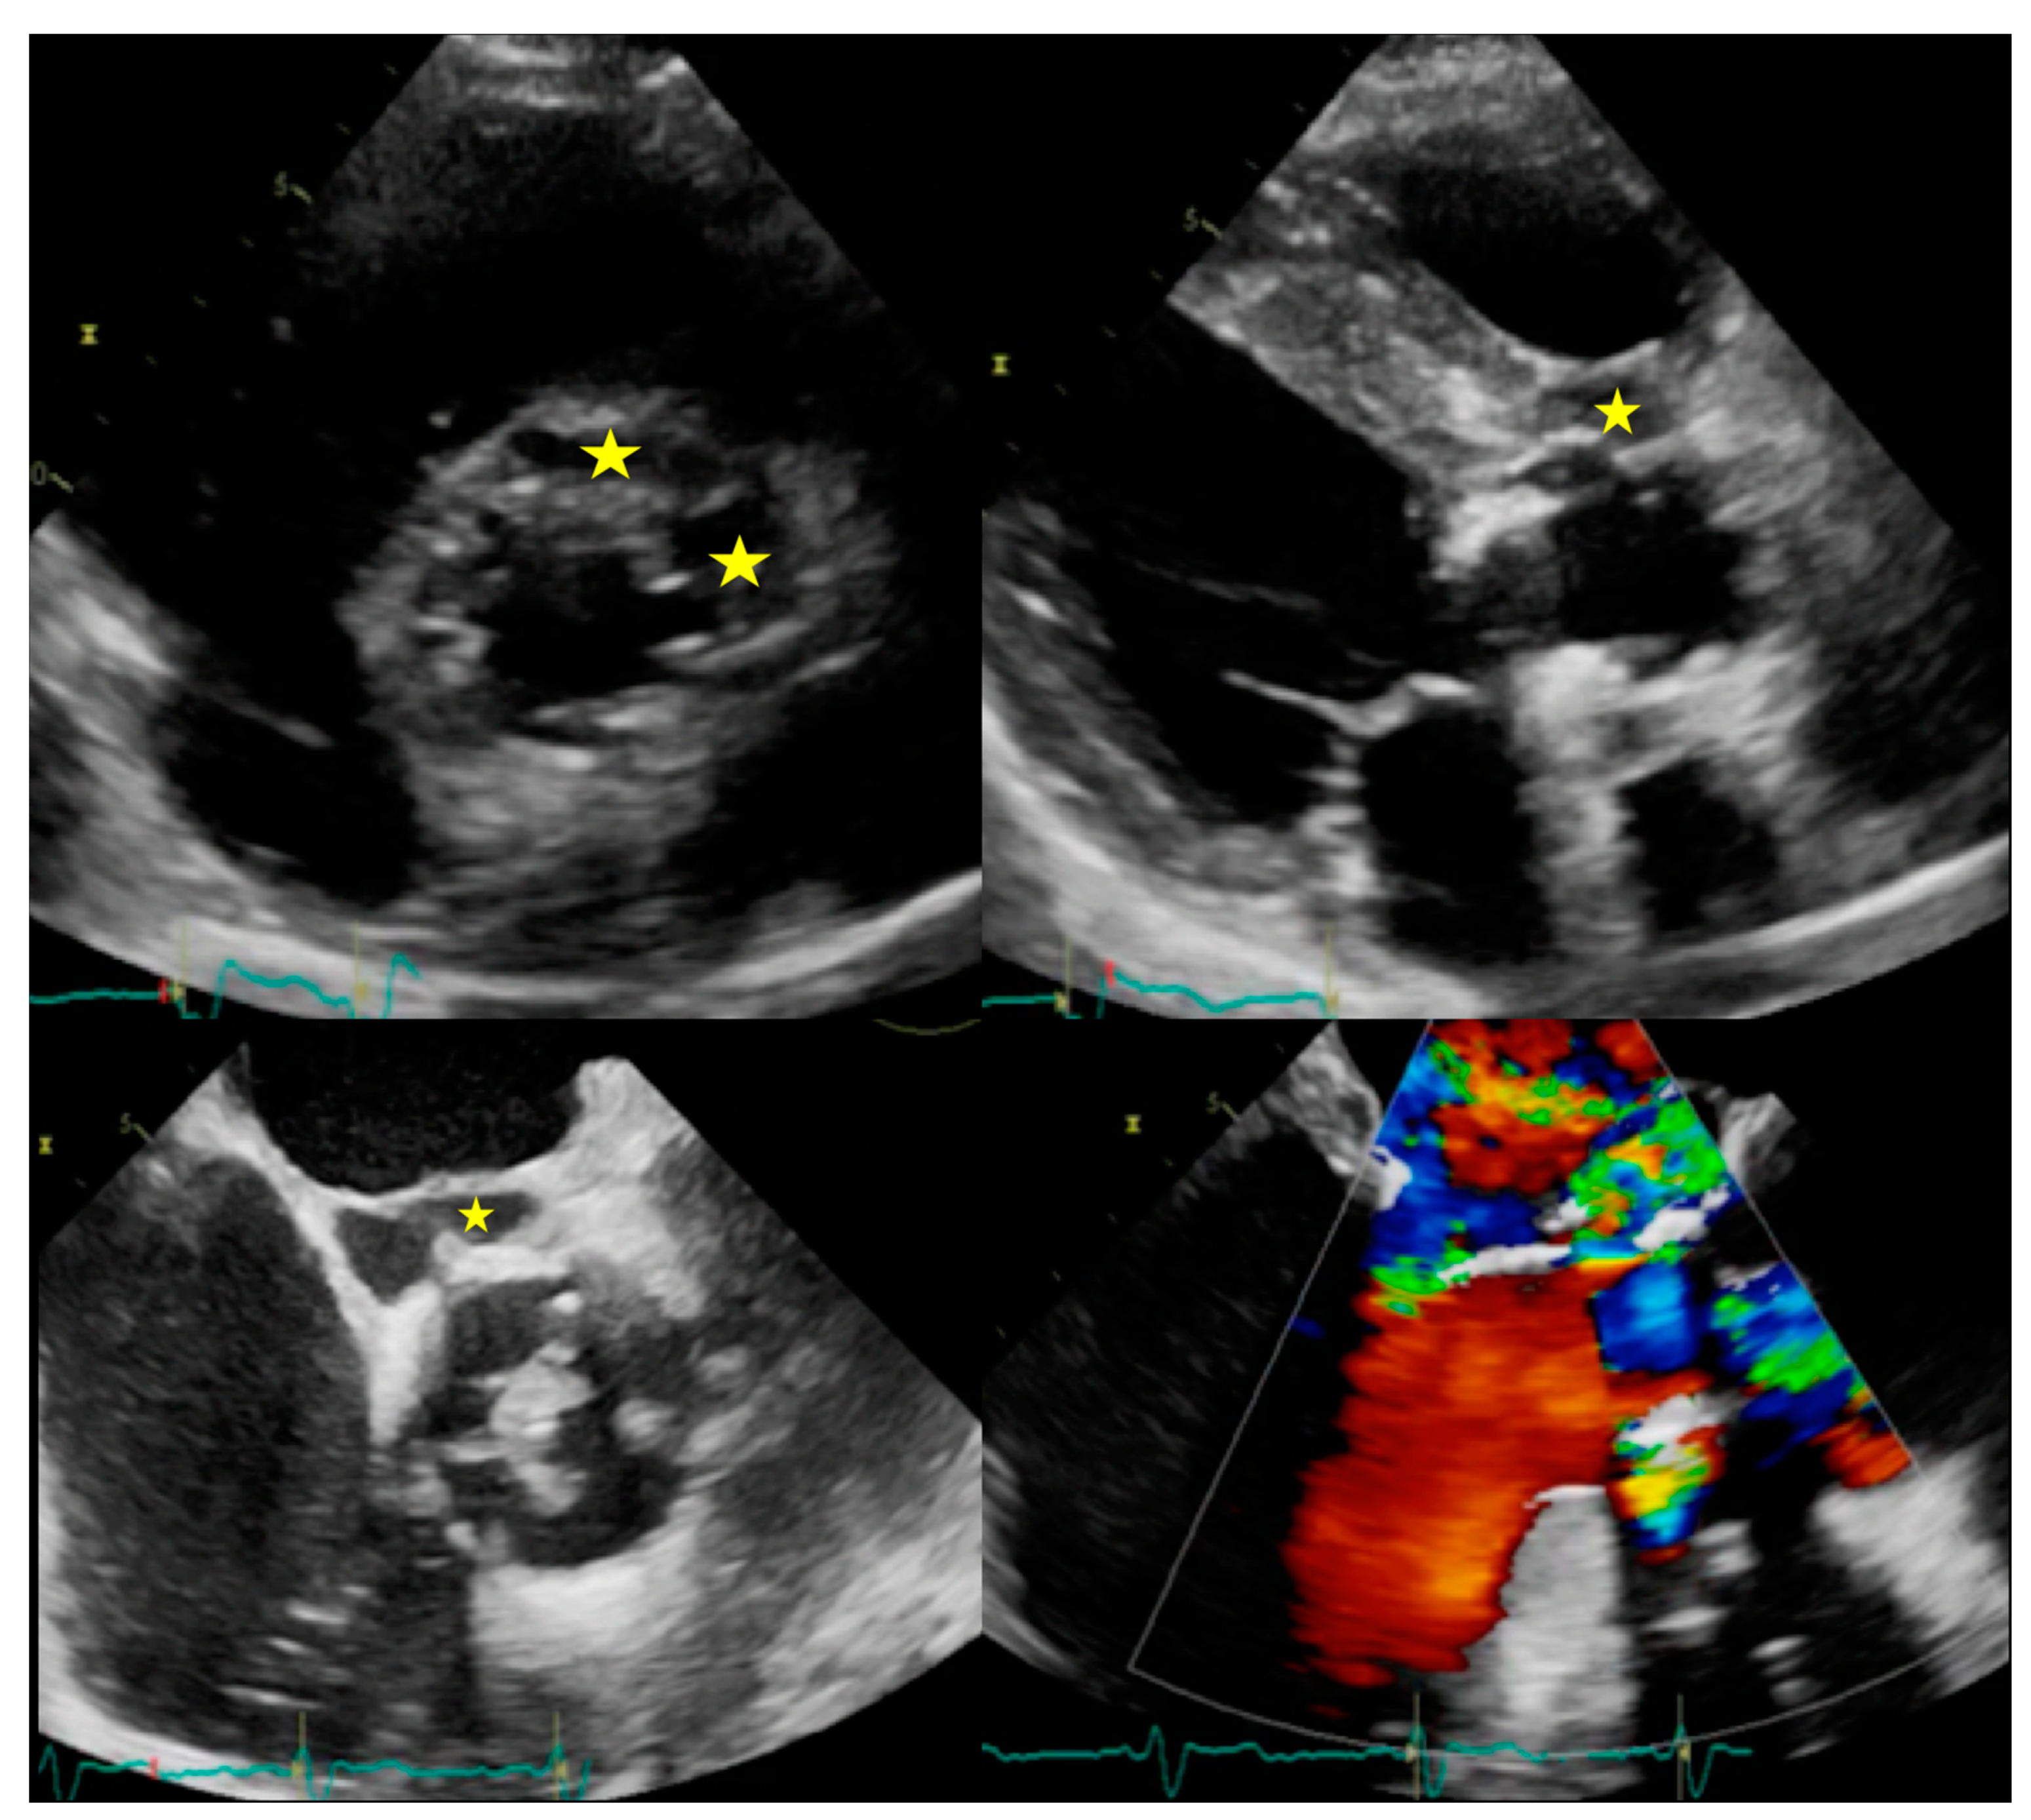

6.2. When to Ask for TTE and When to Ask for TOE

| PVE | Routinely used for follow up; it allows sequential assessment of prosthesis function. TOE is often required to correctly assess the prosthesis. | Limited by prosthetic material artifacts (i.e., acoustic shadow). Early complication (i.e., abscess) can be difficult to identify. | Identification of complications (paravalvular leakage, abscesses, pseudoaneurysm, dehiscence, and extension to adjacent structures). Capability to visualize large vegetations (>10 mm). | Low image quality for beam hardening artifacts. Limited in assessing small vegetations (<4 mm). | High diagnostic accuracy. Good assessment of perivalvular/periprosthetic complications. Reduction of rate of misdiagnosed PVE. Role in prediction of MACEs. Prognostic significance. | Host reaction may reduce specificity (risk of false-positive studies until 3 months after surgery). | High specificity for infection. Reduction of rate of misdiagnosed PVE. Differential diagnosis between septic and sterile vegetations. | Limited sensitivity for small lesions. | Image quality severely hampered by susceptibility artifacts (especially from mechanical prostheses). | |